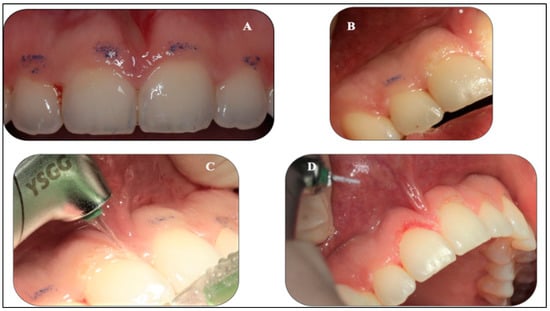

2.5.1. Gingivoplasty Procedure